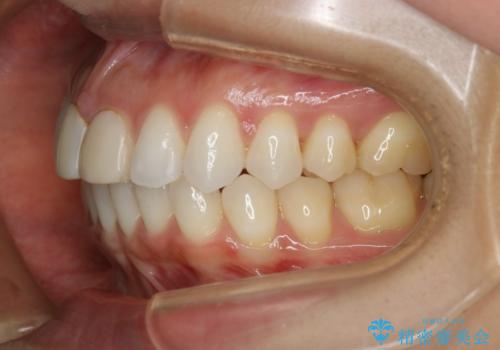

すきっ歯を治したい。インビザライン・ライトによる矯正治療

- 正中離開を気にされて来院された患者様です。

インビザラインでの治療を希望され、正中離開のみ治したいとのことだったので、インビザライン・ライト(片顎)での治療を選択しました。

インビザライン・ライトは枚数が少ないため歯の移動量に限界がありますが、短期間での治療が可能です。